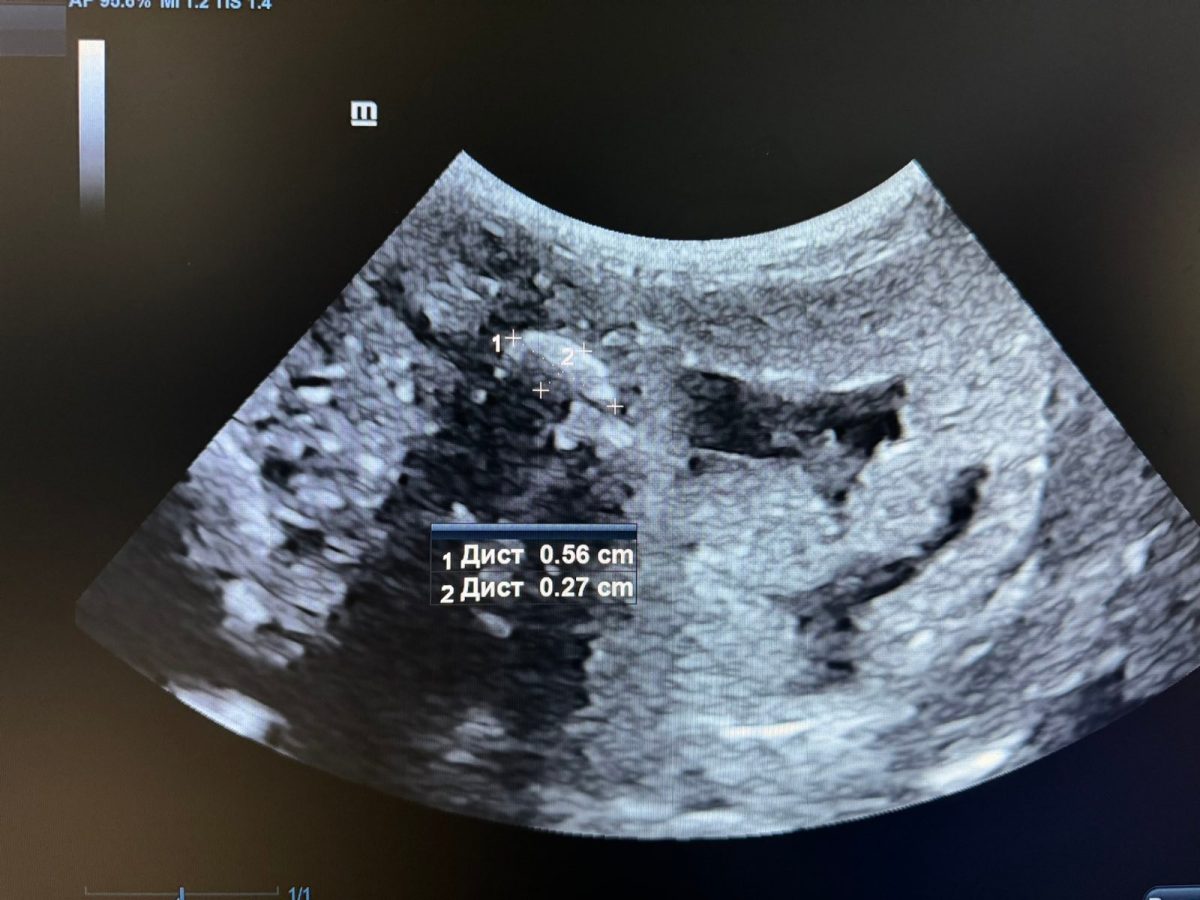

Хозяева экзотического животного пожаловались на вялое состояние зверька. Во время осмотра на рентген-оборудовании выяснилось, что ящерица наелась грунта из террариума. Из-за этого у нее перестал работать кишечник.